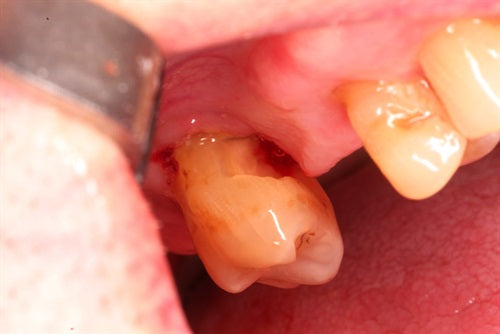

Let's violate biologic width and see what happens

Posted on February 24 2021

#18 has deep cervical decay at the distal Step 1 Patients chief complaint was food impaction. All decay has been removed Step 2 DL margin was flush with the bone... Read More